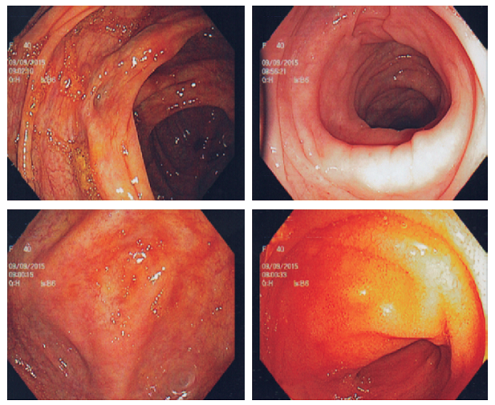

La paciente es valorada por oncología y se inicia manejo con protocolo R-CHOP (rituximab más ciclofosfamida, hidroxidaunorrubicina, vincristina [Oncovin®] y prednisona) dada la extensión de las lesiones, con excelente evolución hasta el momento. La resolución fue completa después del tratamiento (Figura 5).